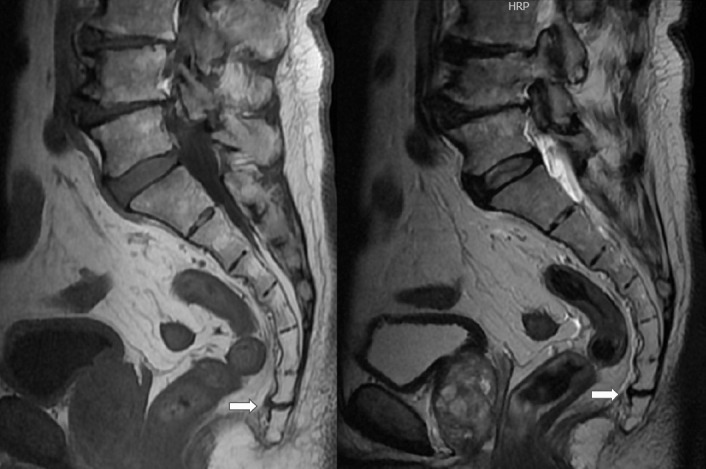

Case report: We present the case of a 64-year-old man with pain in the coccyx and numbness in the perianal area. After clinical examination and imaging evaluation, including plain X-rays and magnetic resonance, coccygeal disc disease was identified. Other findings, such as tumor and fracture were excluded. We decided to undertake conservative management and the pain was eventually relieved. This is the first case report of coccygodynia and perianal numbness attributed to coccygeal disc disease.